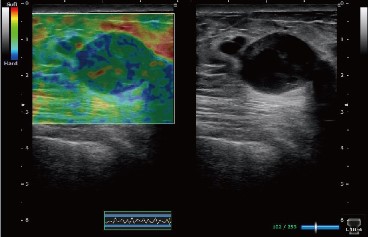

- C)超聲彈性成像功能,不同組織在細微應力作用下產生位移的差異,精細采集后通過自相關計算技術應用不同顏色編碼組織的相對軟硬度,提供病變組織的額外臨床信息,幫助醫生進行病變的評估。